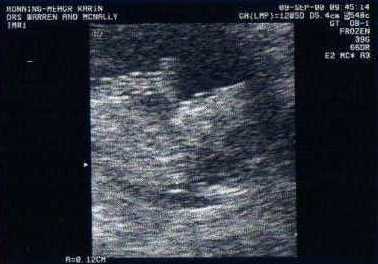

Imogen at 12 week scan I hope for a long and healthy life for you. I hope you enjoy it. It will be hard too, but hopefully your enjoyment of life will help you to cope with the hardships that will inevitably come your way.

Pictured: Imogen at her 12 week scan

We love you deeply. When we saw you on the ultrasound all I could think was that so much promise is held in this tiny, little, few centimetre long blobby bundle of a person with a gloriously solidly beating heart. I wonder who you are?